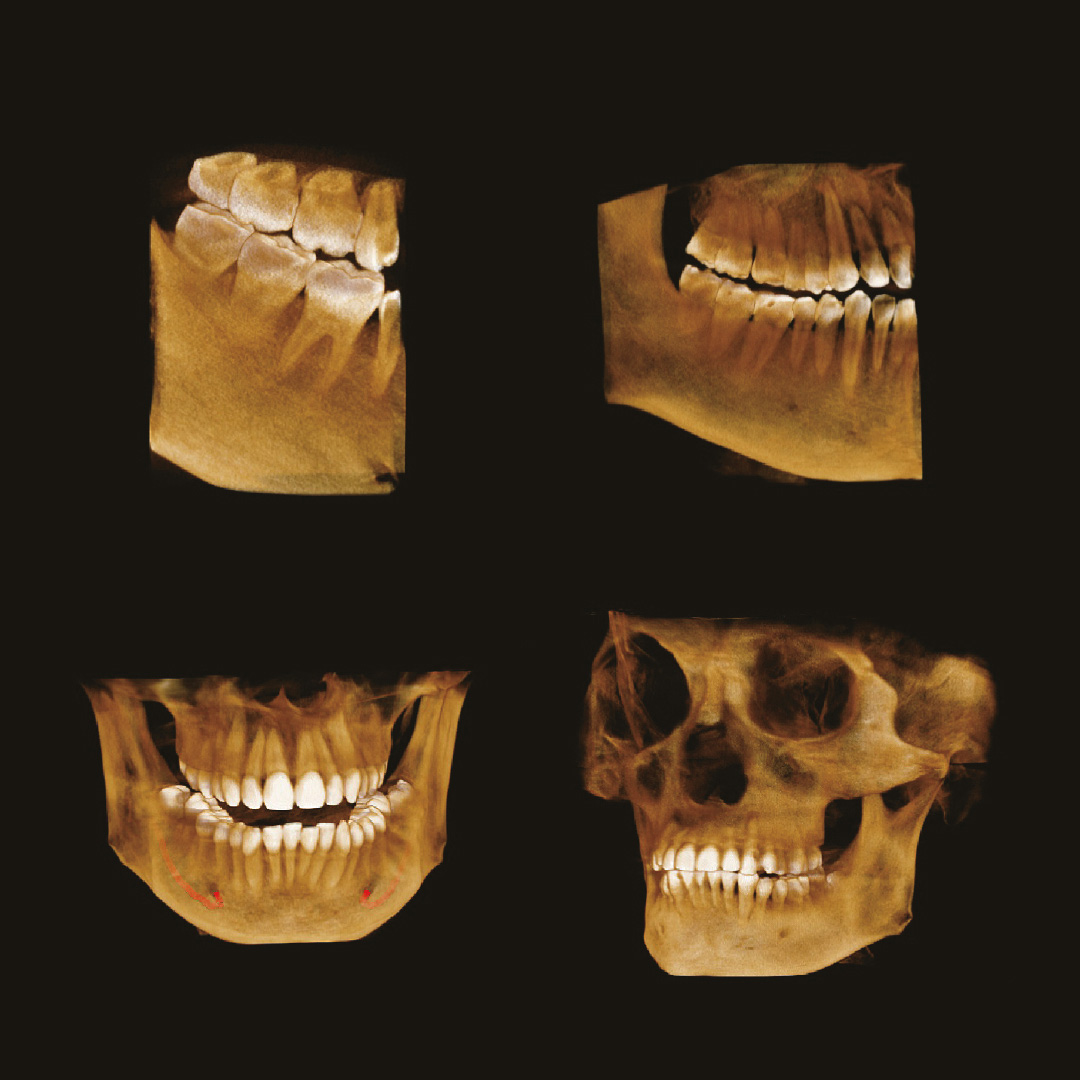

Стоматолог-хирург не способен производить свои манипуляции без снимка КТ, иначе он будет вынужден действовать вслепую, не сумев оценить анатомию области вмешательства.

Стоматолог-ортопед не сможет гарантировать надежность конструкции без правильной оценки стабильности опорных зубов при помощи снимка КТ.

Стоматологу-ортодонту, чтобы правильно простроить план лечения, помимо слепков, так же нужен снимок КТ.